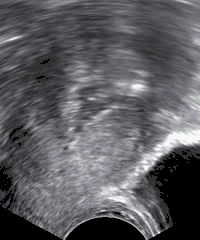

Sonohysterography performed because of postmenopausal bleeding. In serial images, polyps would be less mobile than the freely moving debris seen within the uterine cavity in the image.